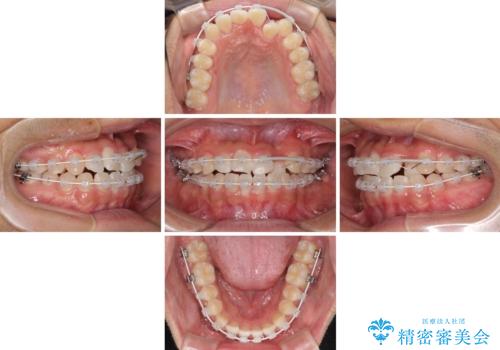

美容歯科でも断られた 著しい前歯のクロスバイトをワイヤー矯正で改善

- 前歯のクロスバイトを気にして来院された患者様です。

美容専門の歯科医院を受診したところ、セラミックでの改善は無理と断られてしまったとのことでした。

歯がすり減って不揃いの形態となっていますが、まずは矯正治療によりクロスバイトを改善することとしました。

治療期間を極力短くしたいとのことで、ワイヤー矯正により治療を行うこととしました。